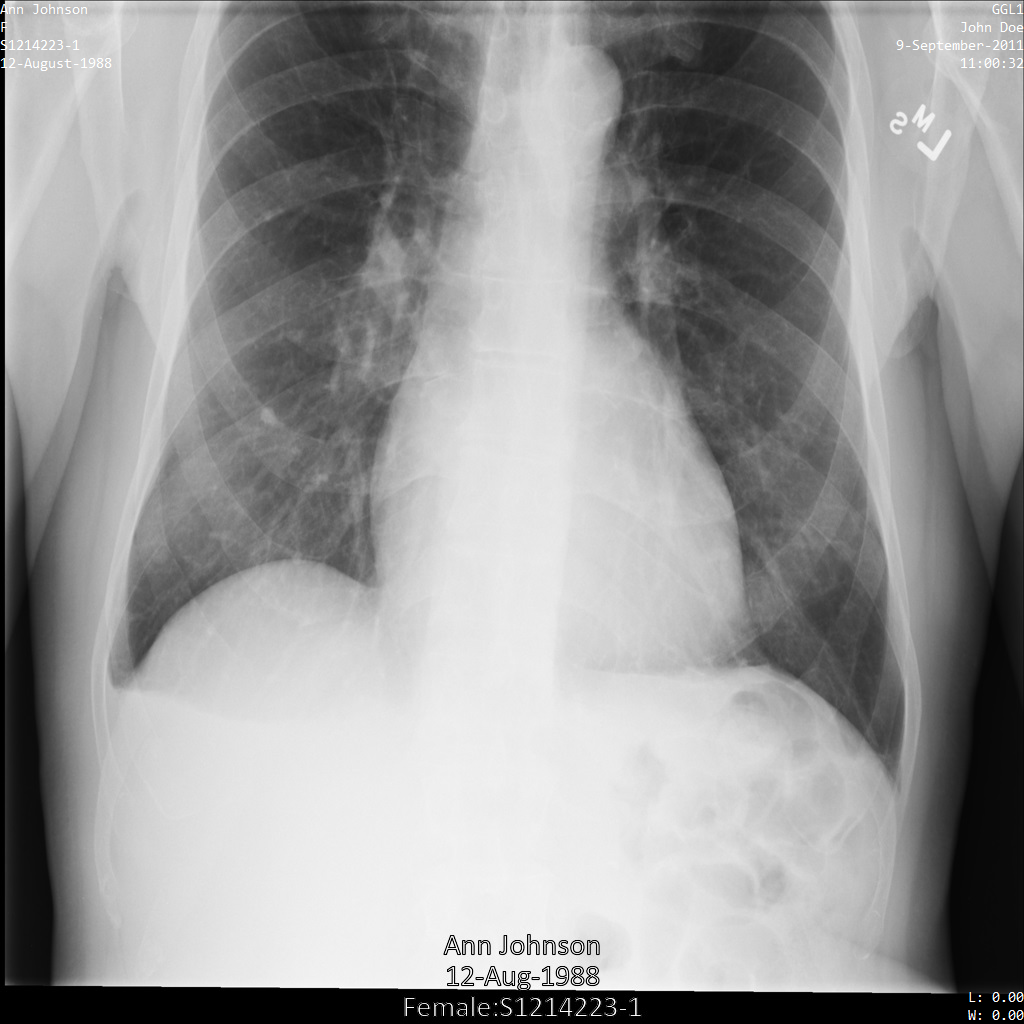

Le sezioni riportate di seguito mostrano l'aspetto dell'immagine nell'istanza DICOM e i metadati nell'istanza.

Immagine di esempio

Alcuni esempi in questa pagina contengono un output dell'immagine deidentificata. Ogni esempio utilizza la seguente immagine originale come input. Puoi confrontare l'immagine di output di ogni operazione di deidentificazione con questa immagine originale per vedere gli effetti dell'operazione: